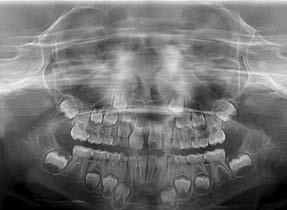

Case treated with EF Kid

Treatment time: 12 months

Jaya

• Skeletal Class I• Hyperdivergent facial typology • Inverted right incisor • Predisposition to previous DMD • Lingual dysfunction during swallowing

Wearing EF Kid

Results: incisor line restored